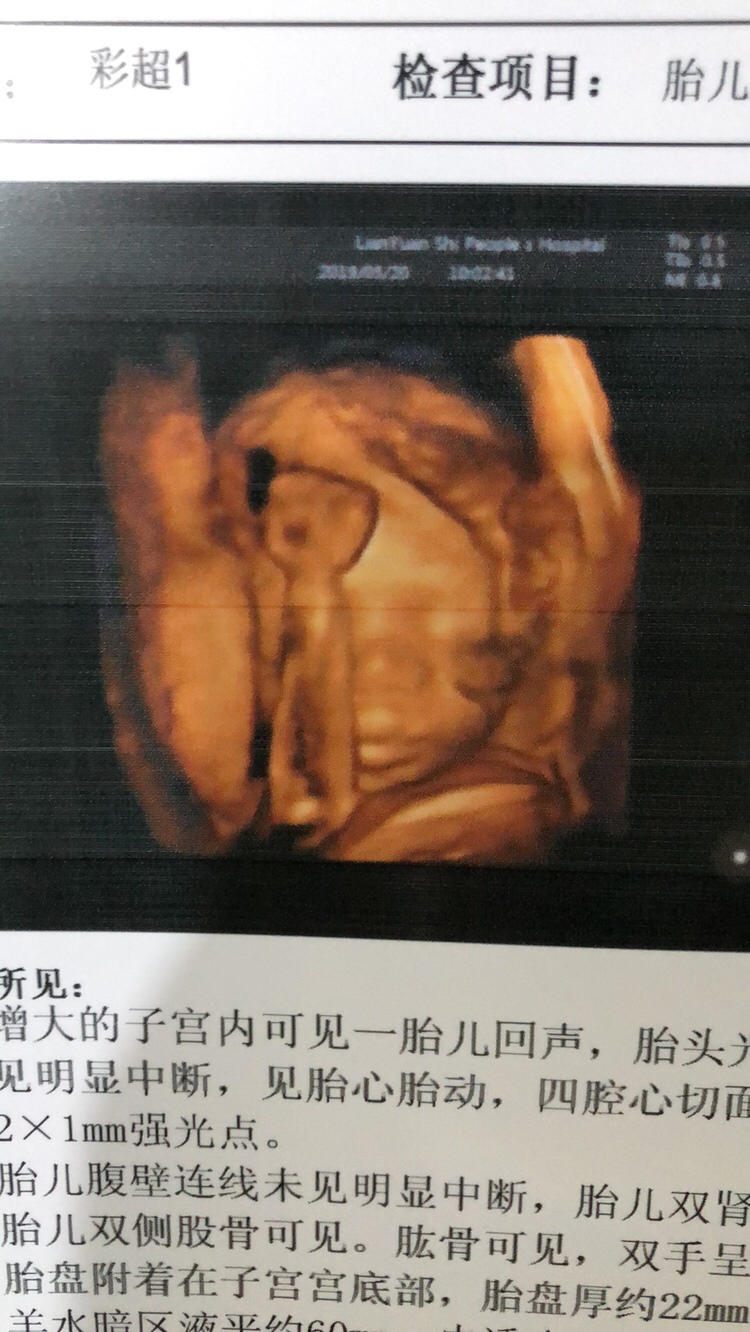

孕26周+3天

孕26周+2天

像男宝